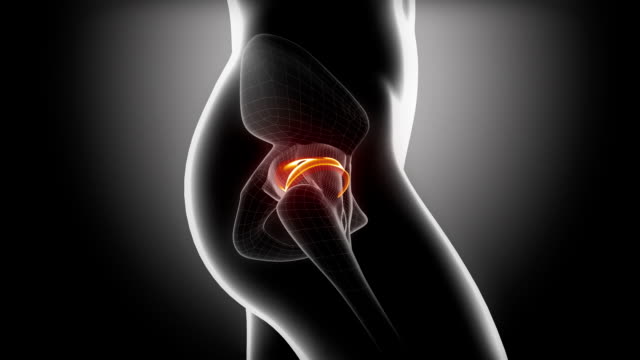

고관절 수술후 회복기간- 수술 후 2주~6주: 물리치료 및 근력 강화

2주~6주 동안은 물리치료와 근력 강화에 집중해야 합니다. 수술로 약화된 근육을 다시 강화하고, 동작 범위와 적응력을 향상시키기 위한 운동을 실시해야 합니다. 이때 꼭 전문가의 도움을 받아야 하며, 개인 차원에 맞는 프로그램을 진행해야 합니다. 무리한 운동을 하지 않도록 조심해야 합니다.